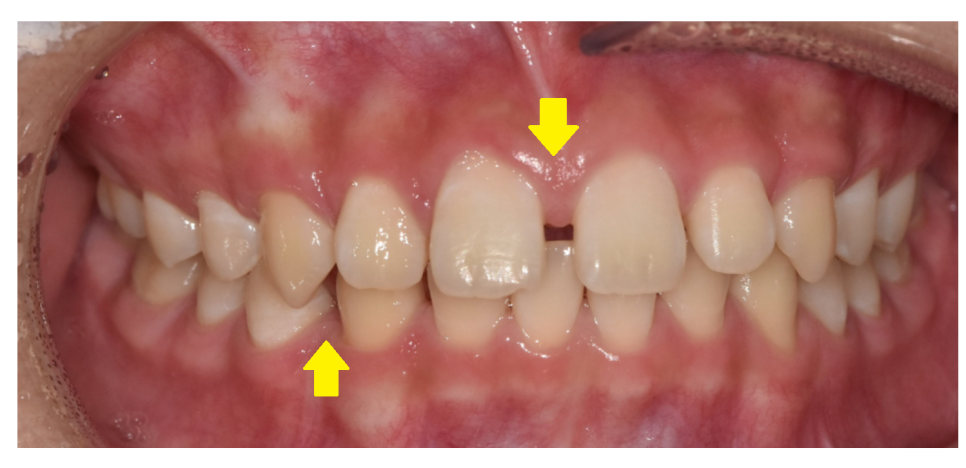

가운데 치아가 눈에 띄게 벌어져있는 환자분